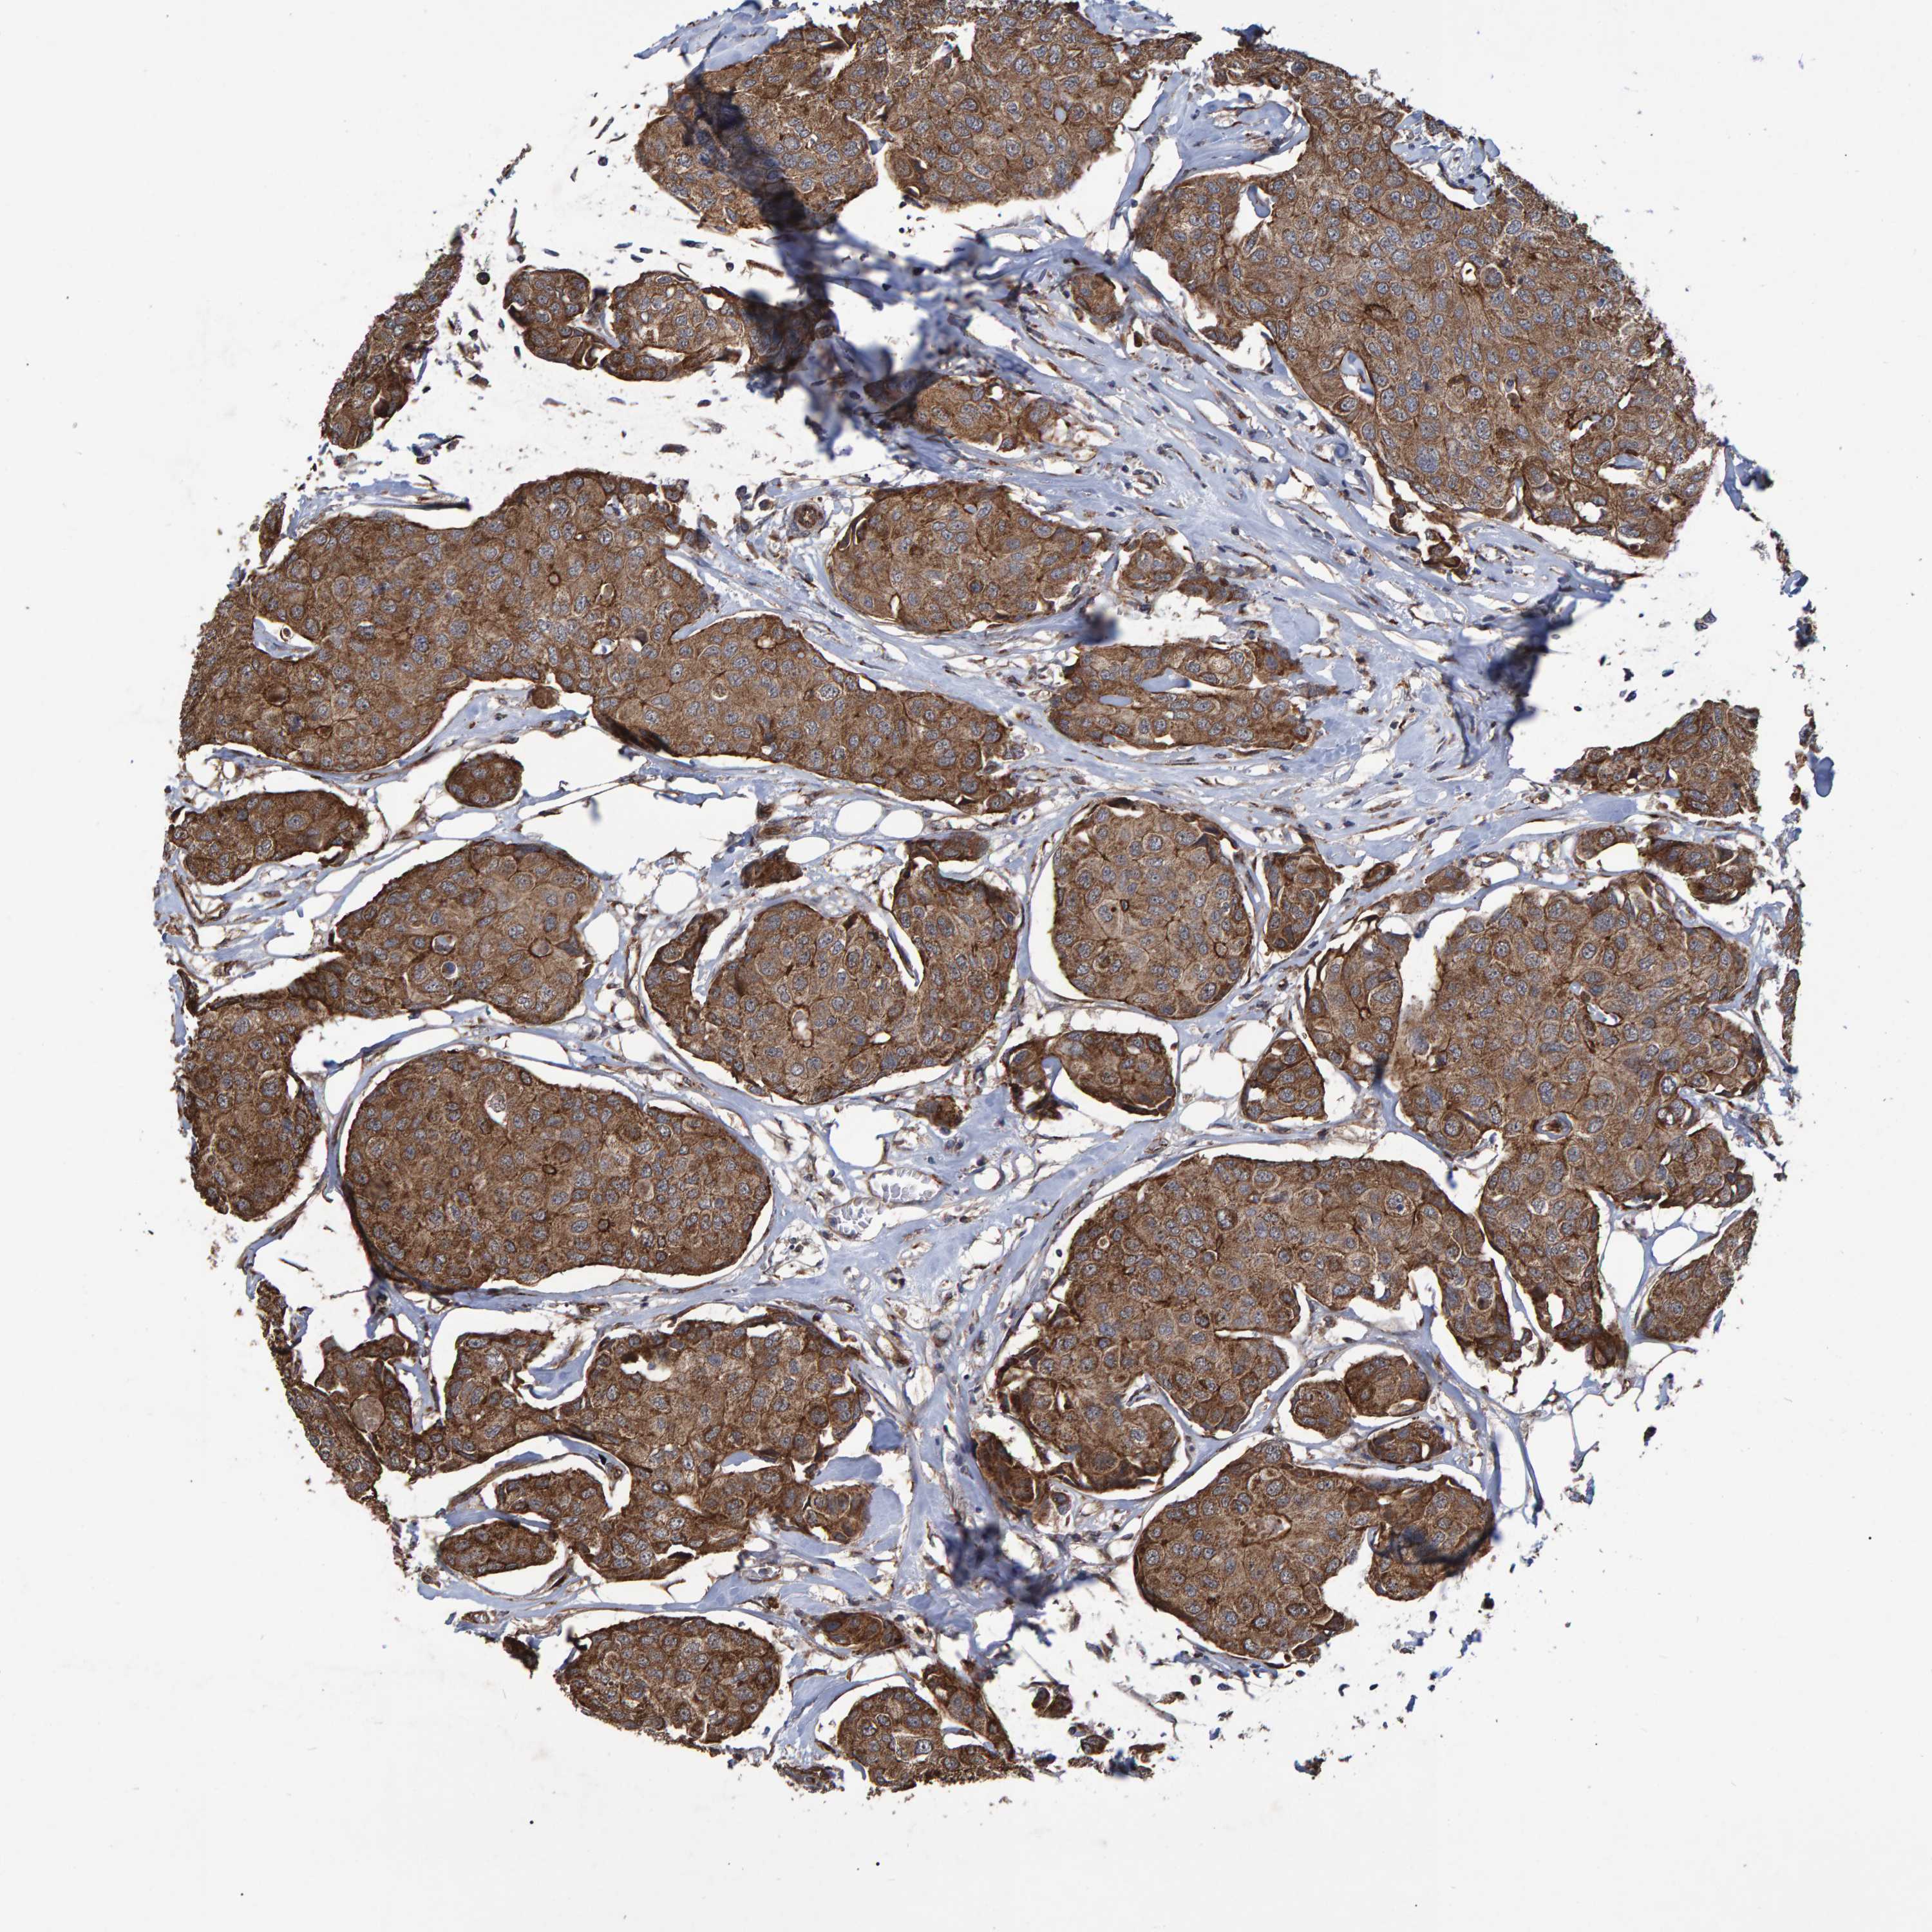

CANCER BREAST CANCER Show tissue menu

BRCA TCGA BRCA VALIDATION PROTEIN EXPRESSION